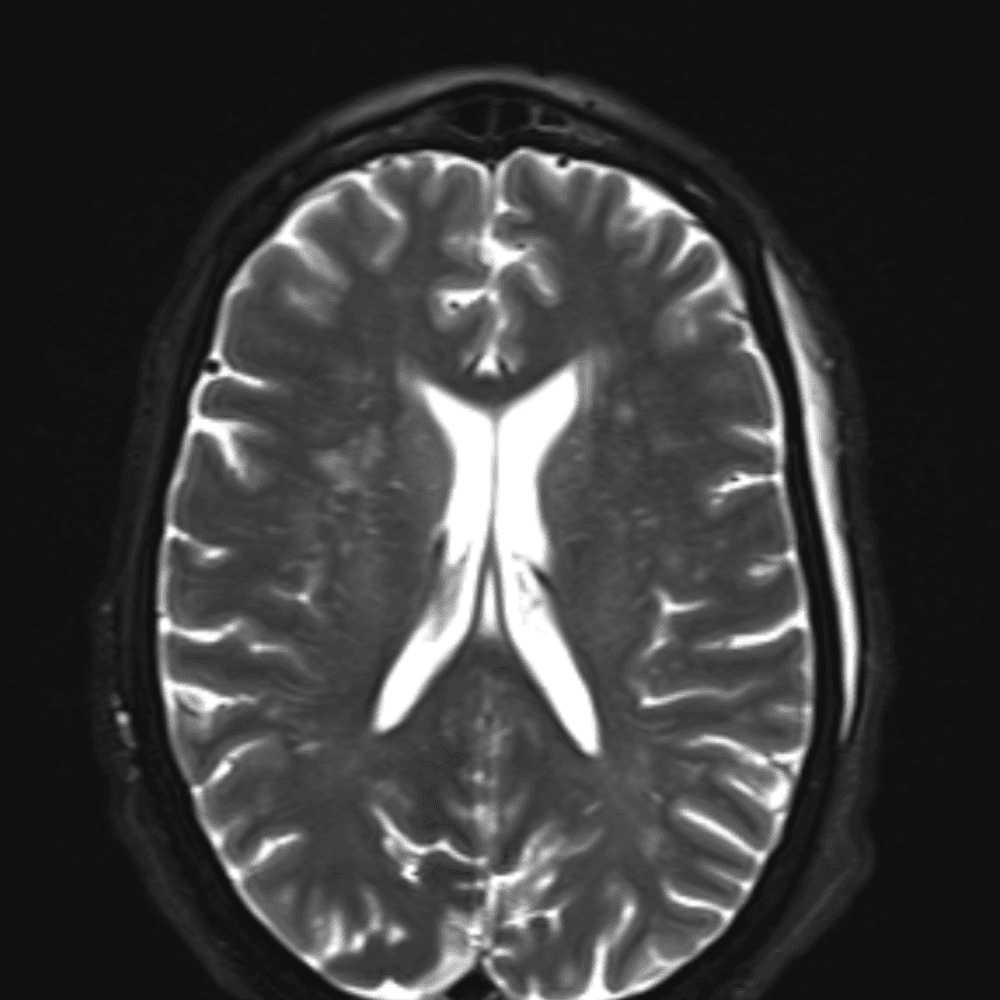

๋‹น์ง ์‹œ ํ”ํžˆ ๋ณผ ์ˆ˜ ์žˆ๋Š” ์‚ฌ๋ก€์˜ ์ „ํ˜•์ ์ธ ์˜ˆ๋ฅผ ํฌํ•จํ•ฉ๋‹ˆ๋‹ค.

39 ์‚ฌ๋ก€

์—ฐ์Šต

๋ฏธ๋ฌ˜ํ•˜๊ฑฐ๋‚˜ ์–ด๋ ค์šด ์‚ฌ๋ก€์™€ ์ผ๋ถ€ ์ •์ƒ ์‚ฌ๋ก€๋ฅผ ํฌํ•จํ•˜์—ฌ ๋‹น์ง์„ ์‹œ๋ฎฌ๋ ˆ์ด์…˜ํ•ฉ๋‹ˆ๋‹ค.

50 ์‚ฌ๋ก€